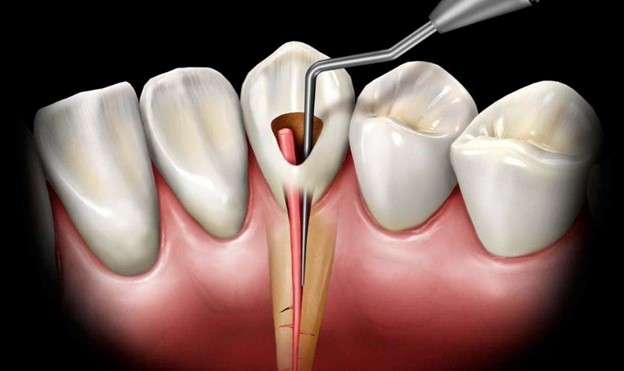

درمان ریشه به یک روش دندانپزشکی اشاره دارد که در آن پالپ عفونی، لایه داخلی دندان که شامل اعصاب و عروق خونی است، برداشته می شود. این عفونت می تواند ناشی از پوسیدگی عمیق، ترک خوردگی دندان یا فرایندهای دندانپزشکی روی همان دندان باشد.

دندانپزشک در طول درمان ریشه، ناحیه اطراف دندان را بی حس می کند، یک حفره کوچک در تاج ایجاد می کند و پالپ عفونی را با دقت خارج می کند. سپس داخل دندان قبل از پر شدن با ماده مخصوص تمیز و ضد عفونی می شود. گاهی اوقات، ممکن است برای بازیابی قدرت و عملکرد آن، یک روکش روی دندان قرار داده شود.

- از بین بردن منبع عفونت: یک دندان عفونی می تواند باکتری ها را به بافت های اطراف پخش کند و به طور بالقوه باعث آبسه و آسیب بیشتر به استخوان فک و سایر نواحی شود. درمان ریشه به موقع، پالپ عفونی، علت اصلی درد و التهاب دندان شما را از بین می برد. این کار از گسترش عفونت و آسیب بیشتر به ساختار دندان و استخوان اطراف آن و ایجاد عوارض شدیدتر جلوگیری می کند.